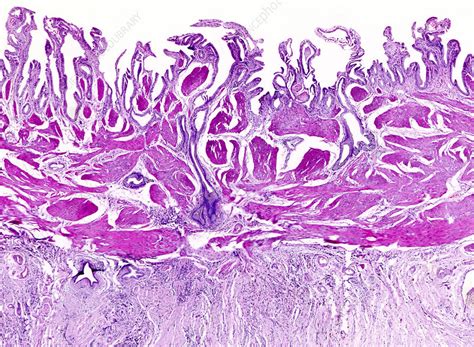

The human body harbors extraordinary biological phenomena, and few are as fascinating and bizarre as teratomas - tumors that can grow teeth, hair, and even fragments of organs. These remarkable growths represent a peculiar intersection of cellular development and medical mystery, challenging our understanding of how cells differentiate and organize themselves.

The term teratoma comes from the Greek word “teras”, meaning “monster”, which perfectly captures the unsettling nature of these tumors. Originating from germ cells - the reproductive cells capable of transforming into various tissue types - teratomas can contain an astonishing array of biological structures:

Teratomas emerge from a disruption in the normal cell differentiation process. Unspecialized germ cells, which typically develop into sperm or eggs, can veer off their standard developmental path. Instead of following a typical reproductive cell trajectory, they begin generating random tissue types, creating these extraordinary tumors.

Remarkable Tissue Diversity

The cellular complexity of teratomas is truly astounding. While most contain benign tissues, they can occasionally include surprisingly sophisticated structures. Some documented cases have revealed teratomas containing: